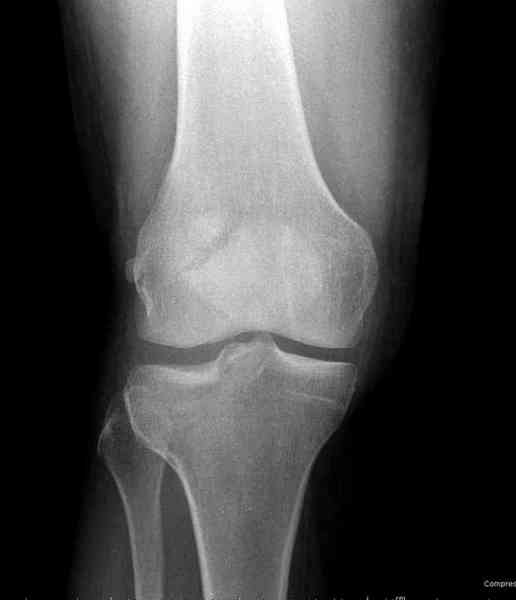

>"мыщелок левой голени будет прооперирован - репозиция, синтез пластиной с костной пластикой, при необходимости удаление повреждённой части мениска"

Для внутрисуставных переломов необходимо идеальное сопоставление, а такая задача без КТ срезов усложнится. Только КТ надо делать после дистракции сустава, иначе нельзя получить объективную информацию.

Около 60% переломов тибиал плато характеризуются мягкоткаными повреждениямм - разрывы суставной капсулы, связок и менисков. Мениск повреждается спереди со стороны перелома.

Основная задача в лечении околосуставных переломов является создание солидного базиса в субхондральной зоне. Пластина подпорка (Butress) или субхондральные перкутанные шурупы в виде плота (Raft) для ранних движении.